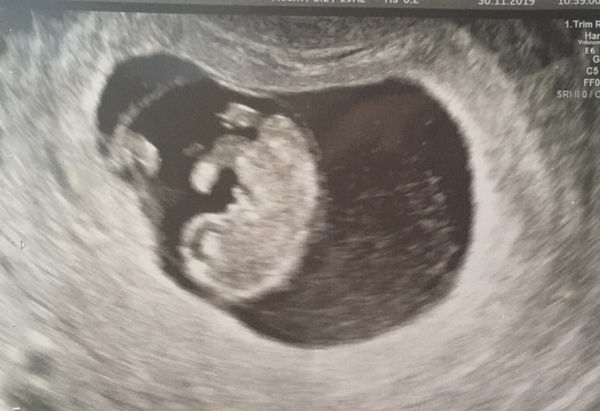

Julilie72 · 01/12/2019 18:13

Thanks, yes pretty excited !! @OlivejuiceU2 @Nelbert19

@RedRobin7 it was internal, and yeah I wasn't sure what we would see at this stage, but it is very clear indeed! :) My OH thinks it looks like Eve in Wall-e, haha so cute.

RedRobin7 · 01/12/2019 18:19

@Julilie72 Internal is much clearer! I've attached my 8 week scan which is external. I'm hoping 10 weeks will be much clearer! I think mine looks like a roast chicken haha!

Lovely scan @Julilie72 It’s so clear! We had an early one yesterday because I was worried about some spotting. I’m 9+1 and we saw the heartbeat. It’s all very exciting!

@RedRobin7 hahaha yes it does look a bit like a roast chicken (more like poussin) ! It's weird, for me they didn't even try external, was straight inside lol.

@PixieN. Wow nice scan picture, lovely bean...glad that the spotting turned out to be nothing bad! :)